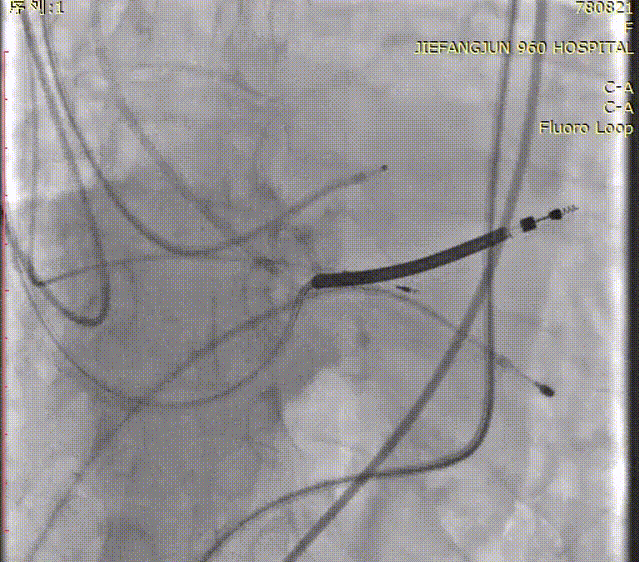

随后,沿加硬导丝送入体外预装好的Prizvalve® THV 23瓣膜,顺利过弓跨瓣,精准定位后,以180次/分快速起搏,待收缩压降到50mmHg时,2-8定位、减容策略进行释放瓣膜。

瓣膜定位造影